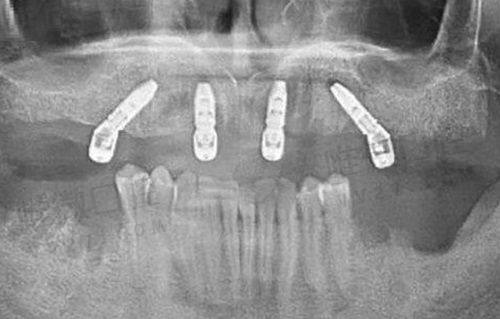

种植牙收费情况

种植牙可是个大项目,对于缺失牙的朋友来说,能修复牙齿的功能和美观。襄阳瑞尔口腔门诊部的种植牙价格根据不同的品牌和种植方式有所不同。一般来说,一颗种植牙的价格在 3000 - 15000 元左右。下面给大家详细列个价格表: